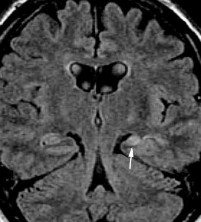

Hình 1.10. Tổn thương não sau chấn thương sọ não dạng nang dịch và tăng sinh thần kinh đệm khu trú

Nguồn trích dẫn: Hiba AH, Lawrence JH. Uptodate. 2018; Topic 14040 [29].